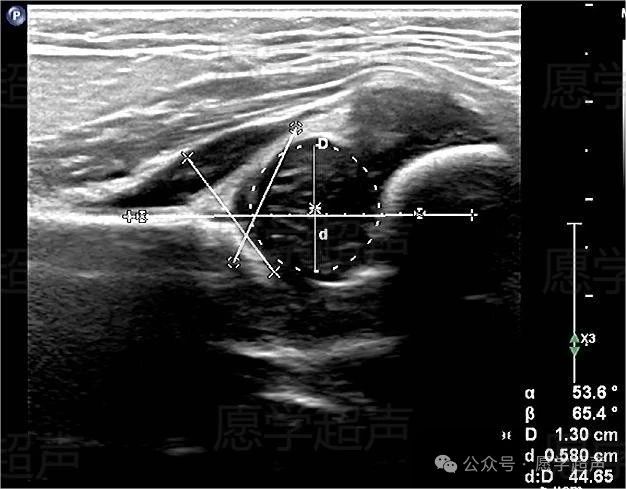

女性患儿,1月龄时因双下肢不等长,要求髋关节超声检查。查体:左下肢较右下肢短约2cm,左侧髋关节外展受限。超声图像髋臼略平直,股骨头与髋臼位置尚正常,盂唇位置偏高,骨性臼顶对股骨头的覆盖率减低,α角53.6°(<60°)、β角65.4°(>55°),骨性覆盖率44.65%。稳定试验时股骨头尚未脱出髋关节。如图:

患儿右侧股骨头与髋臼位置尚正常,盂唇位置正常,α角54.4°(<60°)、β角57.5°(>55°),骨性覆盖率58.16%。

提示不稳定髋关节,建议上级医院复查。

患儿1月半月龄时到省儿童医院复查,结果提示:左侧髋关节骨性髋臼略平直,稳定试验前股骨头与髋臼位置关系尚正常,轴向及内收稳定试验时股骨头略向外上移位。测得α角48.1°(<60°)、β角63.6°(>55°),骨性覆盖率48.9%。右侧髋关节α角65.7°(>60°)、β角53.9°(<55°),骨性覆盖率60.3%,稳定试验阴性,提示:左侧髋关节发育不良,伴不稳定;右侧髋关节声像图未见明显异常。患儿现已佩戴支具进行治疗。